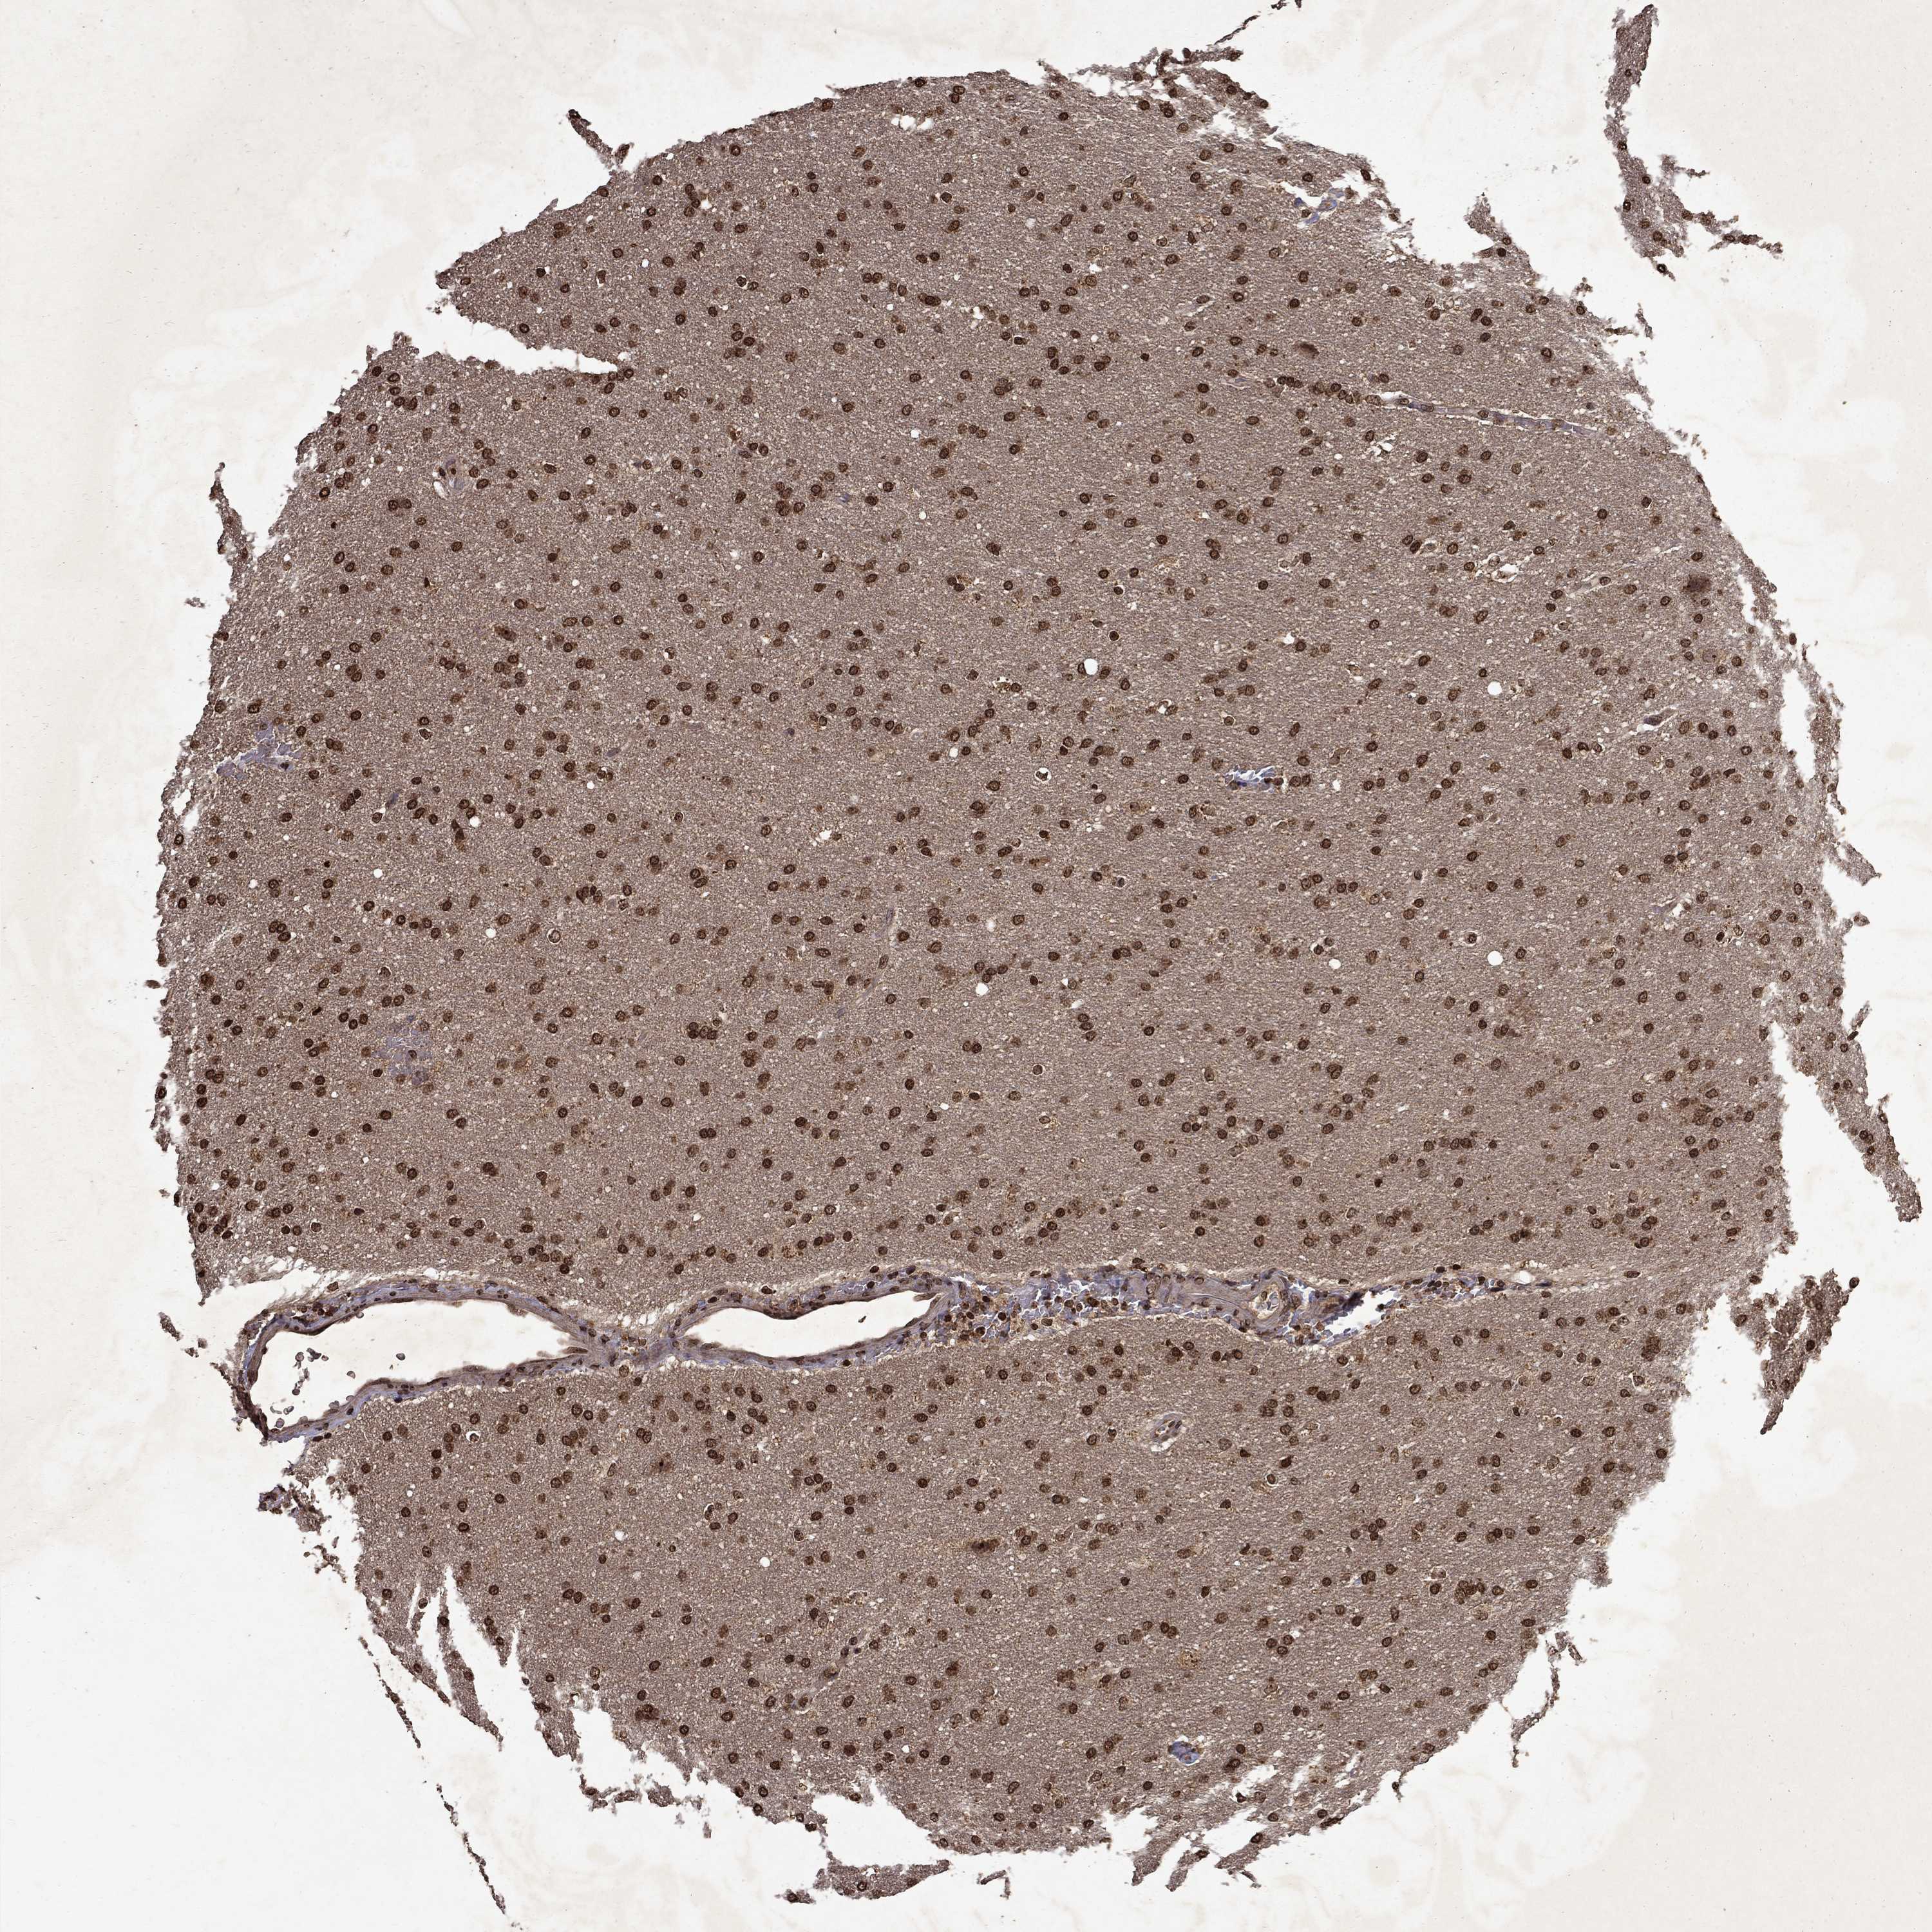

GLIOMA - Protein expressioni

A mouse-over function shows sample information and annotation data. Click on an image to view it in a full screen mode. Samples can be filtered based on level of antibody staining by selecting one or several of the following categories: high, medium, low and not detected. The assay and annotation is described here.

Note that samples used for immunohistochemistry by the Human Protein Atlas do not correspond to samples in the TCGA dataset.

Antibody stainingi

Antibody staining in the annotated cell types in the current human tissue is reported as not detected, low, medium, or high, based on conventional immunohistochemistry profiling in selected tissues. This score is based on the combination of the staining intensity and fraction of stained cells.

Each image is clickable and will lead to virtual microscopy that enables deeper exploration of all samples and also displays staining intensity scores, fraction scores and subcellular localization as well as patient and tissue information for each sample.

Antibody HPA054483

Antibody HPA064504

Staining

High

Medium

Low

Not detected

Intensity

Strong

Moderate

Weak

Negative

Quantity

>75%

75%-25%

<25%

None

Location

Nuclear

Cytoplasmic/membranous

Cytoplasmic/membranous,nuclear

Glioma, malignant, Low grade

Glioma, malignant, High grade

Glioma, malignant, NOS